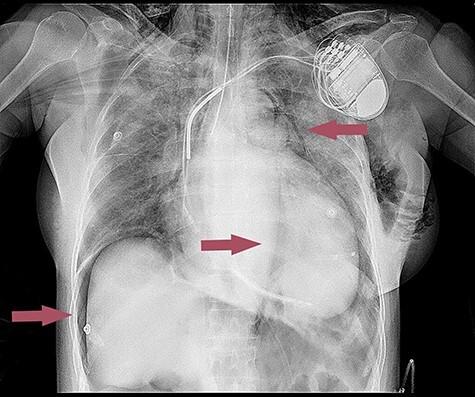

Iatrogenic tracheal rupture is a life-threatening airway complication. It has a very low reported incidence and is more prevalent in women and patients over 50 years of age. The most frequent clinical manifestations of tracheal injury are subcutaneous emphysema and respiratory distress. We report a case of a 65-year-old woman with cardiac resynchronization therapy defibrillator implantation under general anesthesia. Shortly after extubation, dyspnea and subcutaneous emphysema appeared. The X-ray showed pneumomediastinum, pneumopericardium and pneumoperitoneum. The tracheal rupture was confirmed by bronchoscopy. After conservative treatment, the patient's well-being improved, and she was discharged from the hospital in a satisfactory condition.

医源性气管破裂是一种危及生命的气道并发症。其报告发病率极低,在女性和50岁以上患者中更为常见。气管损伤最常见的临床表现是皮下气肿和呼吸窘迫。我们报告一例65岁女性在全身麻醉下植入心脏再同步化治疗除颤器的病例。拔管后不久,出现呼吸困难和皮下气肿。X线显示纵隔气肿、心包积气和腹腔积气。经支气管镜检查确诊为气管破裂。经过保守治疗,患者情况好转,出院时状况良好。